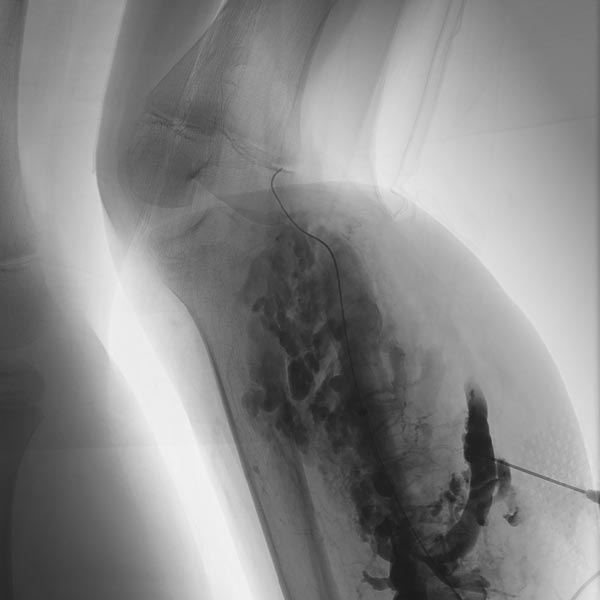

Erneute Sklerosierungsbehandlung 3 Monate nach der ersten Behandlung mit Aethoxysklerolschaum 3 % nach Direktpunktion mit einer Nadel unter sonographischer Steuerung. Die weiter proximal gelegenen Anteile der venösen Malformation sind zum Teil verschlossen, die noch offenen Kanäle deutlich verkleinert. Keine Kommunikation mehr mit dem tiefen Leitvenensystem. Inzwischen war zum Beinlängenangleich rechts eine temporäre Epiphyseodese mit vorübergehender Klammerung der Wachstumsfugen durchgeführt worden.

Es erfolgte eine erneute Punktion weiter proximal am Unterschenkel, da hier sonographisch noch offene Anteile der venösen Malformation nachweisbar waren. Nach Anspritzen kontrastieren sich nur noch wenige, kleinlumige Abschnitte der Malformation. Sklerosierungsschaum in den Hohlräumen des distalen Anteils der Malformation (als Aufhellung sichtbar).

Die letzten verbliebenen offene Gefäßkanäle des venösen Malformationsanteils werden in einer weiteren Sklerosierungssitzung jetzt noch mit Alkoholgel verschlossen (Phlebographie in Direktpunktionstechnik). Dieses Sklerosierungsmittel ist besonders effektiv und durch seine hohe Viskosität weniger in der Gefahr durch verbliebene Verbindungen ins tiefe Leitvenensystem abzuströmen.

Durch Injektion des nicht kontrastgebenden Alkoholgels kommt es zu einer Verdrängung des Kontrastmittels durch das Alkoholgel.